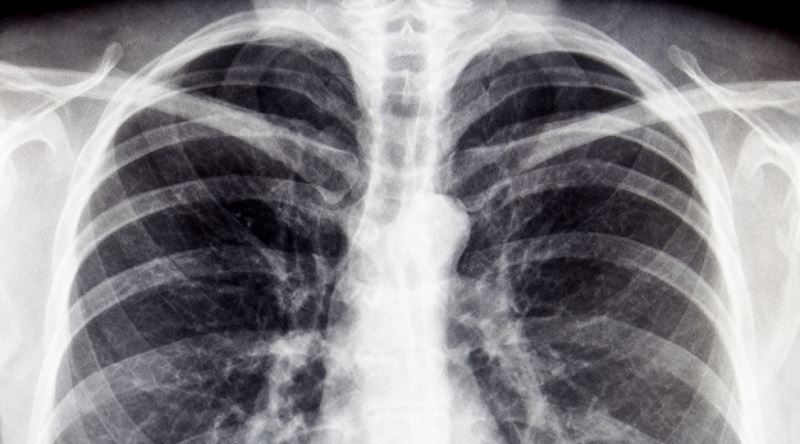

akciğer filmi

görüldüğü üzere hastanın sadece kaburga kemikleri görülmekte, akciğer ya da kalp gibi dokulara dair neredeyse hiçbir şey yok.